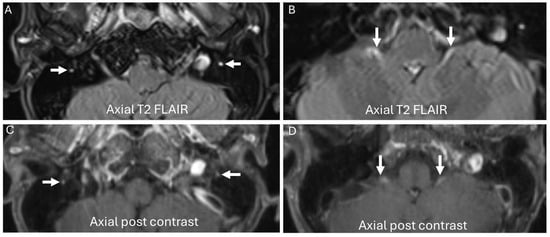

3.4. Chronic Ataxic Neuropathy, Ophthalmoplegia, IgM Paraprotein, Cold Agglutinins, and Disialosyl Antibodies (CANOMAD)